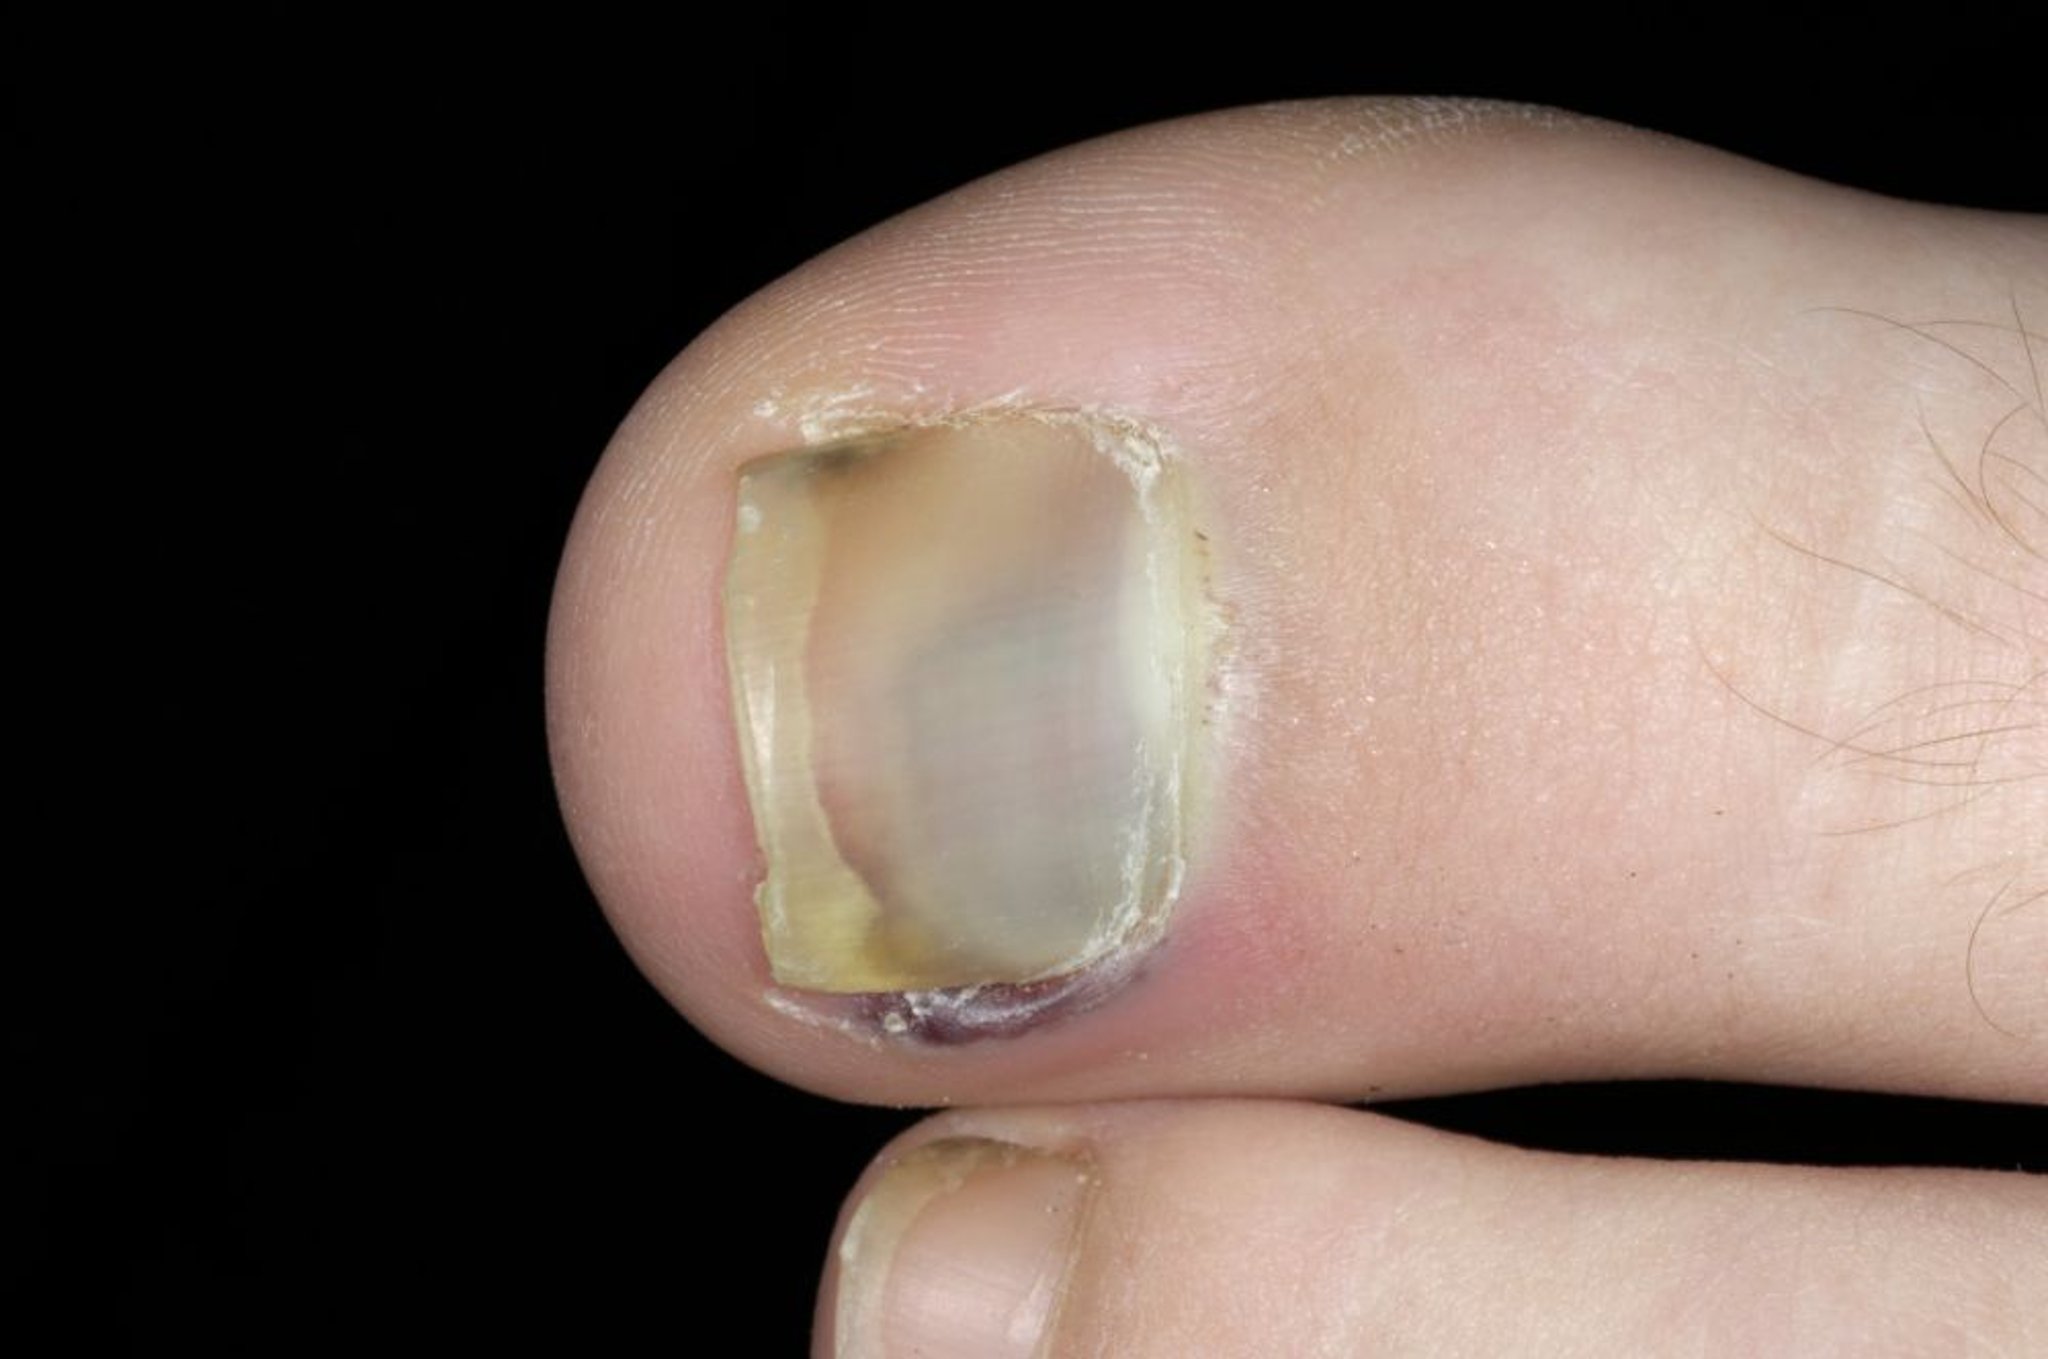

Dieses Foto zeigt Blutungen unter dem Nagel des großen Zehs.

DR P. MARAZZI/SCIENCE PHOTO LIBRARY

Schmerz, Schwellung und Empfindlichkeit sind häufig. Subunguale Hämatome (zwischen der Nagelplatte und dem Nagelbett) sind ebenfalls häufig, insbesondere wenn es sich um eine Quetschverletzung handelt (siehe Abbildung ).

Eine gebrochene Zehe ist normalerweise schmerzhaft und geschwollen. Es bildest sich gewöhnlich ein subunguales Hämatom, insbesondere wenn der Zeh zerdrückt wurde.